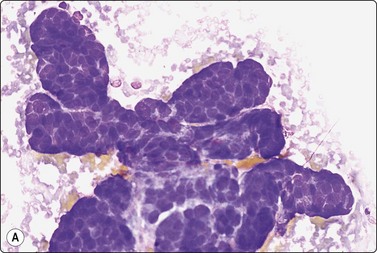

Fig. 7.4 Non-neoplastic glandular breast tissue and low-grade duct carcinoma

High-power view, Pap-stained smears; (A) Bimodal population in smear from non-neoplastic breast; (B) Single and clustered cells in low-grade carcinoma; some single cells probably stromal (Pap, HP).